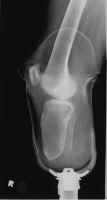

The images shown demonstrates a BKA of acceptable length. The patient is

wearing a prosthesis.